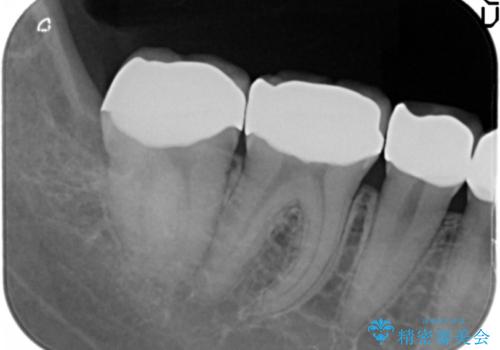

精査したところ、ほとんどの歯が保険内のレジンで充填されており、咬み合わせも悪く咬合していない歯もありました。

虫歯をしっかりと治療したのち、オールセラミッククラウンによる補綴治療を行いました。